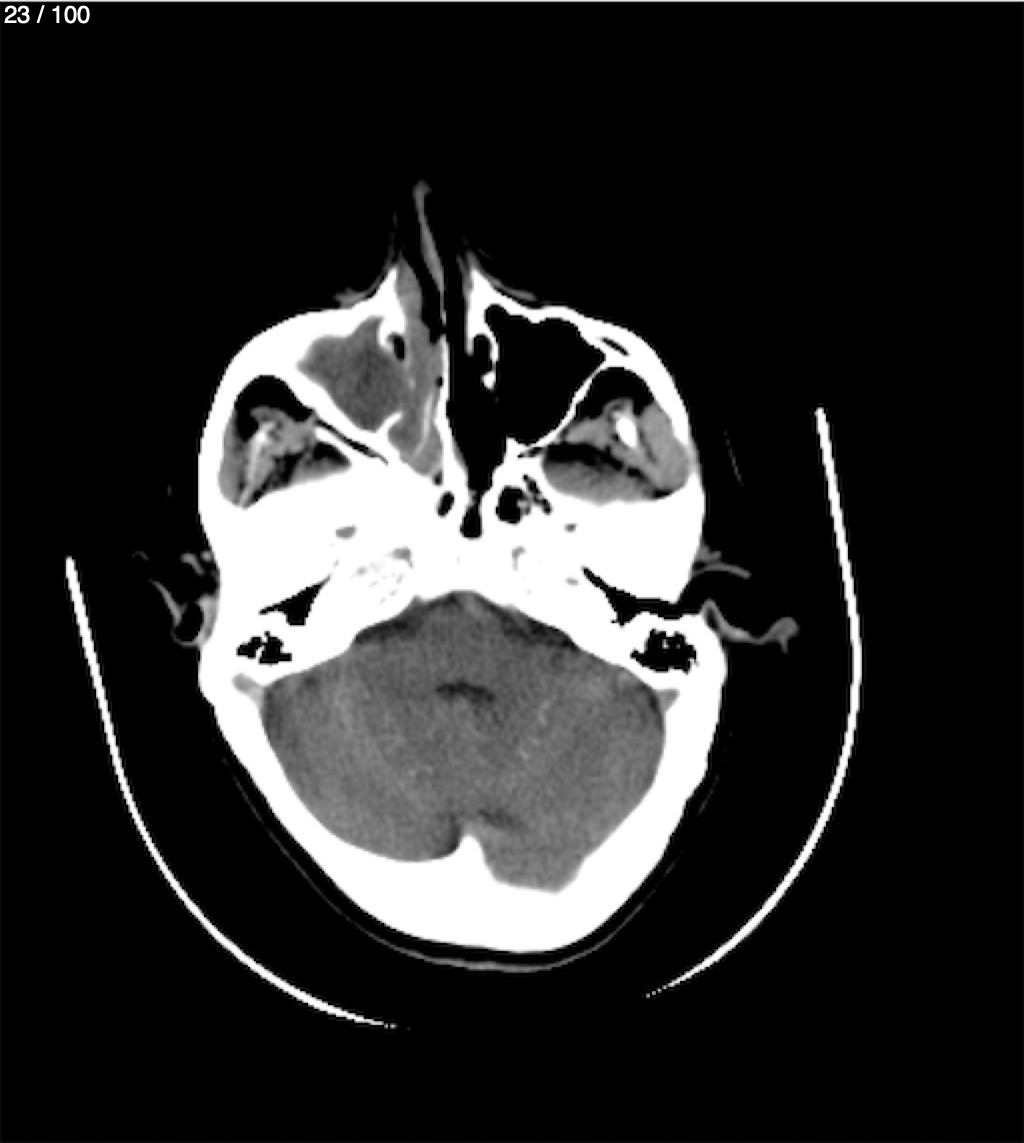

Valentin Perez Gomez 69A - T.C Craneo